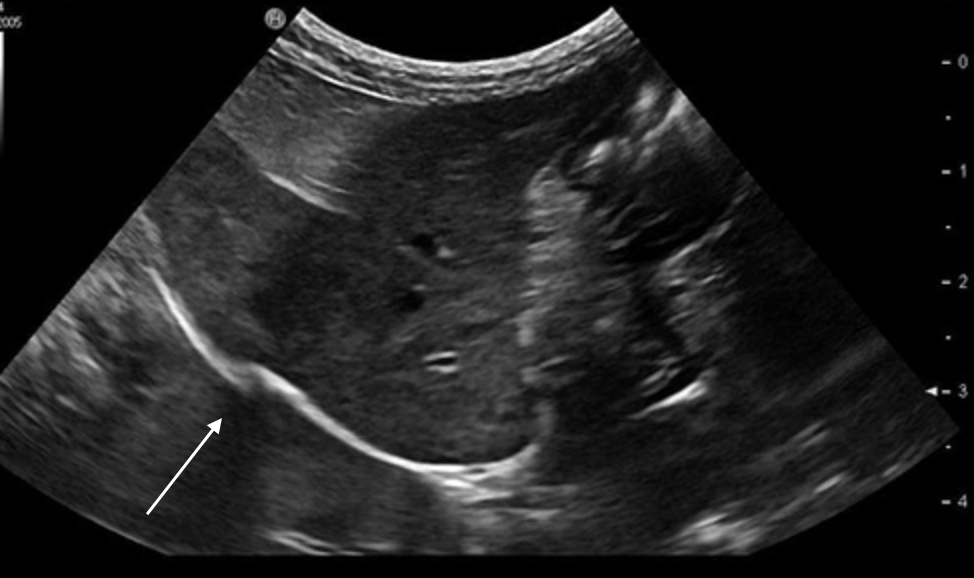

Name this artifact.

What is the cause of the artifact? How would you (try to) fix it?

Edge shadowing artifact: Refractive artifact that occurs at the edge of a large curved boundary with a different speed of sound than that of the surrounding tissues

FIX: spatial compounding, change angle of insonation